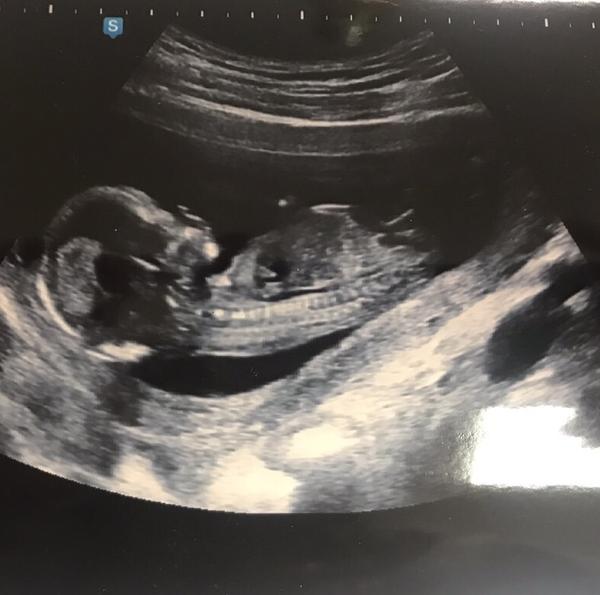

Teď už jsem v 16 tt a byla mi potvrzená 100% holka 😀. Takze doktorka se opravdu spletla v tom 13 tt, jak tvrdila 100% kluka, tak prý měla turecký sed a primotal se tam nejspíš prst 😀.

Přikládám foto ultrazvuku holčičky v 16tt pro ostatní maminky pro porovnani, je to zaber zespodu jakoby na prdku s roztazenyma nozkama 😉.

@kristyna14092013 nahore na stránce mam dost podobnou fotku a je to holčička. Ty citis co?

@kristyna14092013 holčička. pohlavní hrbolek je souběžně s osou páteře. kdydy výrazně čněl nahoru, je to kluk 🙂

@lussinka88 já tipují holčička 👍❤